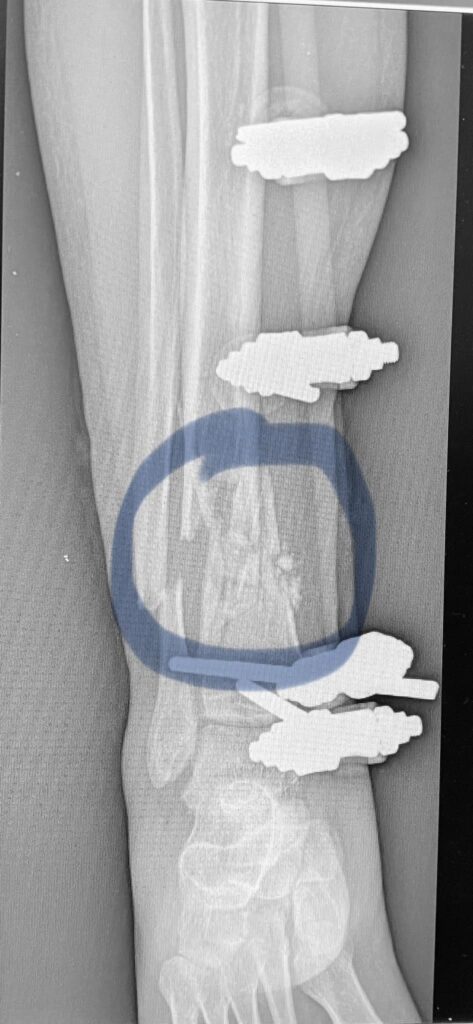

На первом фото – это заменитель кости, на втором (черно-белом, дабы Фейсбук не волновался) поверх собственной кости пациента насыпаны гранулы заменителя кости. Они блескучие такие. Недаром этот заменитель кости называют ещё и «биостекло». Потом – рентгенограмма после заключительной операции.

На фото вы видите, как этот заменитель кости выглядит на рентгенограмме голени с дефектом кости. И как мы засыпаем его в рану. BONALIVE дорог (10 см кубических вот в таком вот контейнере в виде шприца около 500 евро; кстати, госпиталь по мере сил тоже закупает его; но на одного раненого часто нужно 60-70-80 «кубиков» и больше; никакой бюджет не потянет).